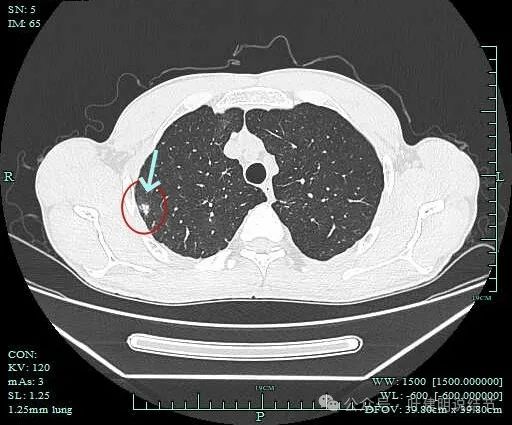

点状高密度之外,蓝色箭头示周围有淡磨玻璃影。

风轻云淡磨成分明显且轮廓不清。中间的点状高密度显得不够致密,缺乏收缩力。

边缘区仍有淡磨形态的晕

病灶1影像印象:

此灶从连续层面上看,是自右上前侧斜行向左下后侧延伸的,整体病灶偏长条些,而且有晕、有淡磨成分,实性部分缺乏收缩力或膨胀性,更符合炎性病灶的恢复期或吸收不全的阶段。